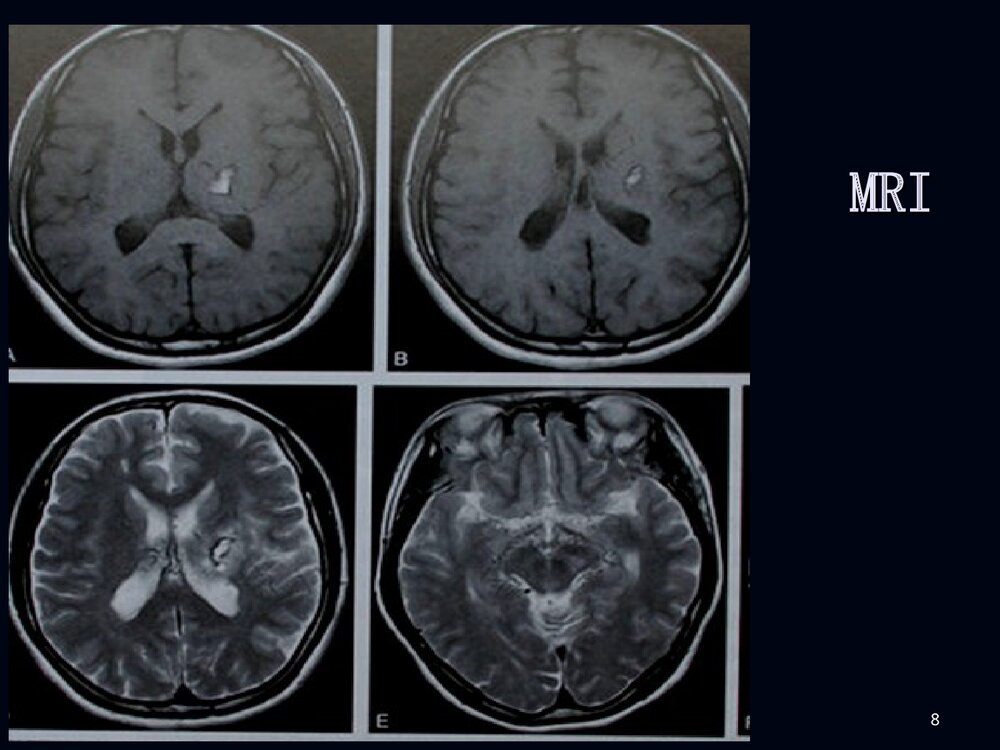

1烟雾病临床和影像诊断烟雾病临床和影像诊断2男性,男性,2020岁突发剧烈头痛岁突发剧烈头痛11小小时时3脑室穿刺脑室穿刺引流后增引流后增强强CTCT4MRIMRI5MRAMRA67病例病例22F、38Y,右侧肢体无力伴言语不清24天8MRIMRI910病例1DSA11烟雾病烟雾病病例2脑底异常血管网1213烟雾病烟雾病概述概述病理病理分型、分期分型、分期临床表现临床表现影像表现影像表现诊断诊断鉴别诊断鉴别诊断治疗治疗14概述概述烟雾病是以颈内动脉虹吸部或大脑前、中烟雾病是以颈内动脉虹吸部或大脑前、中动脉起始部缓慢的进行性的自发性狭窄或闭塞、动脉起始部缓慢的进行性的自发性狭窄或闭塞、并在脑底出现异常的小血管网为特点的一种脑血并在脑底出现异常的小血管网为特点的一种脑血管病。管病。在脑血管造影时,脑底...